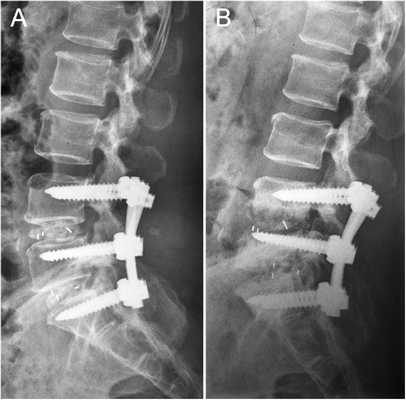

Кейджы межпозвоночных дисков поясничного отдела.

В преобладающем количестве подобные операции заключаются в достижении полного обездвиживания патологических уровней за счет прочного скрепления двух или более позвонков ригидными конструкциями. Это позволяет позвонкам с течением некоторого времени (от 3 до 6 месяцев) срастись между собой и образовать единый неподвижный костный блок. То есть, на прооперированном поле подвижность между позвонками будет заблокирована, а человек сможет нормально двигаться и ходить, не испытывая при этом боли и прочих неврологических расстройств.

Если выполняется одноуровневая фиксация, искусственно созданная обездвиженность будет неощутимой. При многоуровневой технике стабилизации, что требуется не так уж и часто, позвоночник в определенных местах утратит гибкость, из-за чего некоторые элементы движений станут выполняться несколько в ограниченной амплитуде.

Итак, в первом случае процедура представляет собой замену на имплантат (цена 70-100 тыс. рублей) одного или сразу нескольких проблемных позвонков позвоночника, которые предварительно удаляются. После внедрения соответствующих размеров протезного устройства производится его фиксация к верхнему и нижнему здоровым позвонкам. Во втором случае, если речь стоит о необходимости извлечения только деформированного диска на определенном уровне, который существенно дестабилизировал прилежащие к нему позвонки или сократил высоту между ними, выполняется вживление динамического или неподвижного межтелового имплантата в пространство между смежными костными телами. Обо всех возможных вариантах замены позвонков и межпозвонковых дисков мы расскажем далее.

Операция предполагает возвращение смещенного тела на место и его надежную фиксацию, которая стабилизирует весь позвонок правильном положении. В целях фиксации используется специальный имплант, заполненный костным аутотрансплантатом. Он устанавливается на место изъятого межпозвонкового диска, а после закрепляется к смежным позвонкам металлической конструкцией. С течением времени позвонковые тела прочно срастаются между собой, образуя неподвижное соединение, благодаря чему на данном уровне больше не будет происходить патологического сдвига.

Межтеловой кейдж для фиксации позвонков

Чтобы операция дала наилучший результат, часто используется межтеловой кейдж, который должен отвечать таким требованиям:

- обеспечивать стабильность тел позвонков;

- гарантировать сохранение нормальной высоты межпозвоночных дисков, что позволяет избежать компрессии нервов;

- быть изготовленным со специальным пространством через которое, можно вводить костный цемент, искусственную костнозамещающую крошку или препаратов увеличивающих рост костной ткани ;

- Корригировать и фиксировать боковой (сагиттальный) и передний (фронтальный) баланс позвоночника;

- Удерживать нагрузку которая ложиться на ось позвоночника.

Безусловно, предельно качественное выполнение ТПФ обеспечивается при применении устройств 3-го поколения. Современные имплантируемые кейджи позволяют надежно зафиксировать патологически измененный сегмент позвоночника и устранить болевой синдром, обусловленный его остаточной подвижностью.